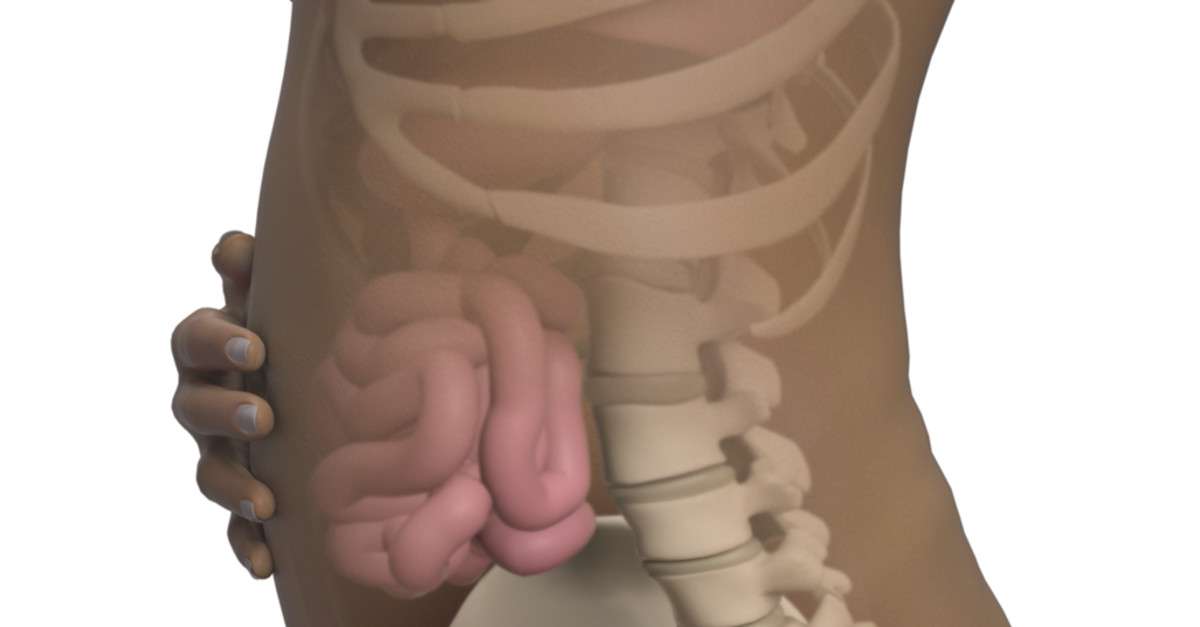

Медицинские аспекты мекония в околоплодных водах